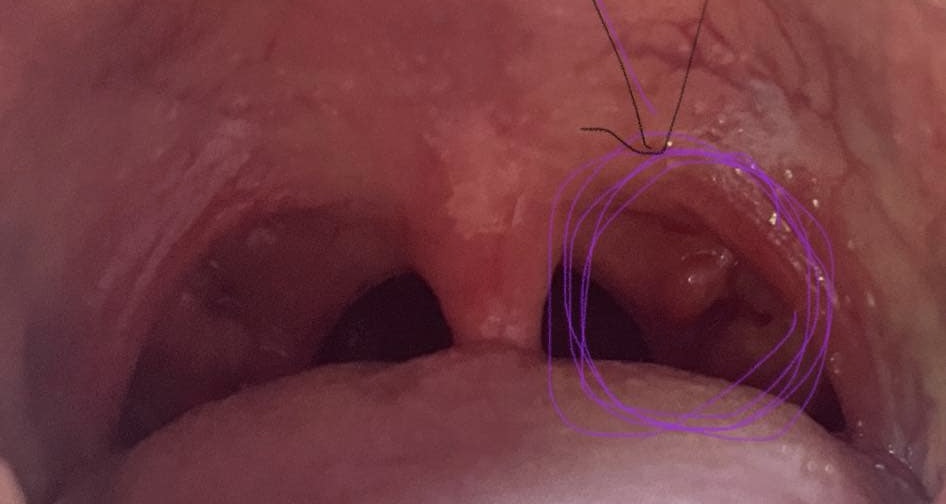

เป็นติ่งนูนใกล้ลิ้นไก่ ตรงท่อมซิล แบบนี้ปกติไหม ไม่มีอาการอะไรค่ะ เพิ่งจะเห็นไม่รู้ว่าเป็นนานแล้วหรือเพิ่งเป็น